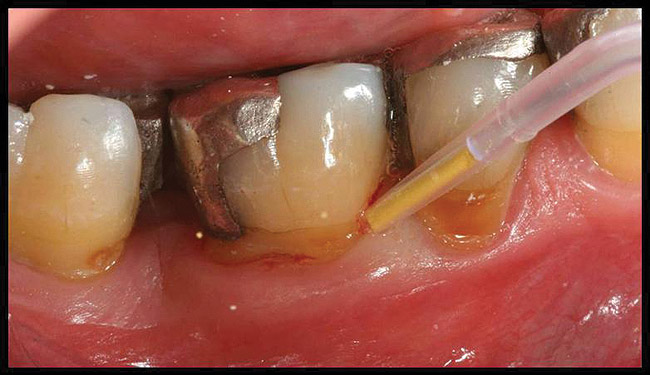

The use of adjunctive treatments, such as introduction of additional oral hygiene aids, use of locally delivered antibiotics (such as minocycline microspheres [Arestin®, OraPharma Inc, Warminster, PA]), host modulation therapy (low-dose doxycycline [Periostat]), subgingival irrigation, or prescription mouth rinses may be helpful in controlling signs of persistent disease.

Locally delivered, controlled-release agents are a popular treatment adjunct and serve to augment scaling and root planing to help improve outcomes. Clinical studies have shown that use of such agents can provide an average of 0.5-mm additional pocket depth reduction over scaling and root planing alone, so the practitioner must weigh the cost-benefit ratio of using these products in each patient situation.39,40 A guideline for the appropriate use of locally delivered antimicrobials has been provided by the American Academy of Periodontology.41 These materials are contraindicated in patients with (1) multiple 5-mm pocket depths in one quadrant; (2) anatomic defects caused by periodontal diseases (intrabony defects); and (3) when the previous use of locally delivered agents has failed to control disease. As noted before, a follow-up reevaluation always should be completed to evaluate the success of any therapeutic intervention, generally at 4 to 6 weeks after treatment has been rendered30,31 (Figure 3A through Figure 3D).

Figure 3a   patient in posttreatment periodontal maintenance program returned with (A) isolated bleeding on probing;

Figure 3a

Figure 3b   patient in posttreatment periodontal maintenance program returned with (B) a 5-mm probing depth noted at a maintenance visit.

Figure 3b

Figure 3c  The site was treated by localized scaling and root planing, followed by use of Arestin (minocycline microspheres).

Figure 3c

Figure 3d  The resolution of inflammation and bleeding on probing on the reevaluation appointment 6 weeks later.

Figure 3d